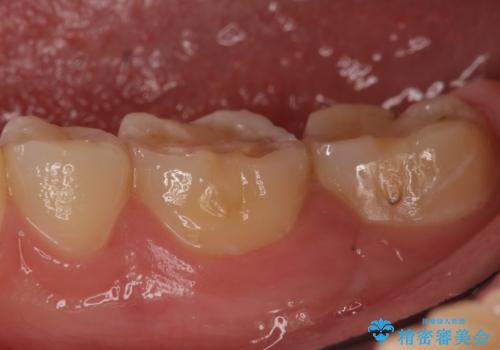

- 冷たいものを飲むと、左下奥歯がしみると来院された方の症例です。

検査の結果左下6が虫歯になっていたため、セラミックインレーによる修復を行いました。

当院のセラミックインレーはemaxという強度と審美性に優れた材料を使用しています。

またプレス方式でインレーを製作しているため、削り出しで製作するCADCAMより優れた適合性も持ち合わせており、虫歯が再発しにくい修復物です。